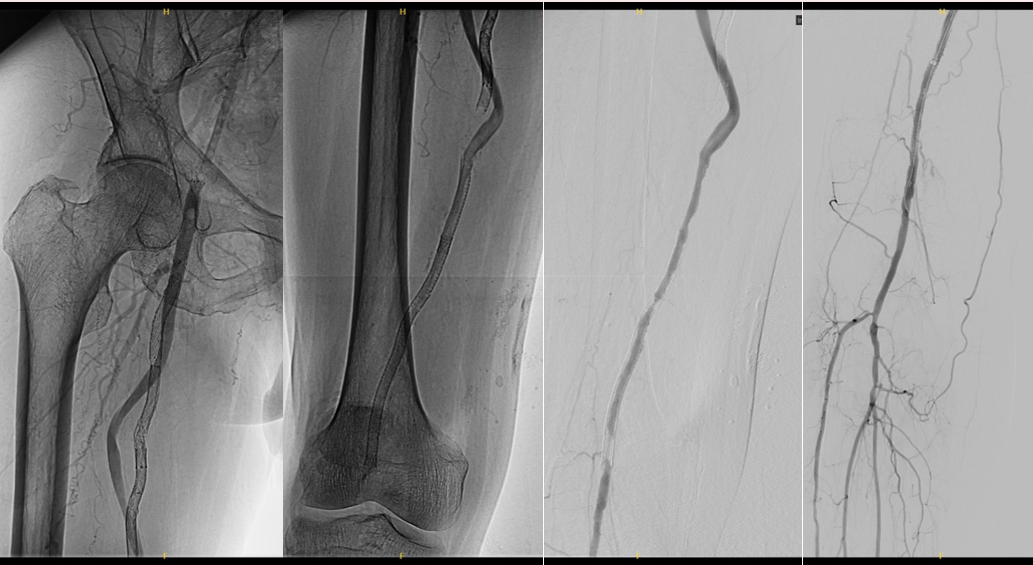

★ 激光消融

图:使用2.3mm导管,参数设置从45mj/mm²、45Hz开始,逐步增加至60mj/mm²、60Hz。

★ 球囊扩张

依次使用不同规格球囊进行扩张

Saber 2--200mm球囊

Saber 5--300mm球囊

Reewarm 5--220mm球囊

Saber 2.5--150mm球囊

★ 术后结果

血管造影显示管腔明显改善,血流恢复良好

图:术后造影